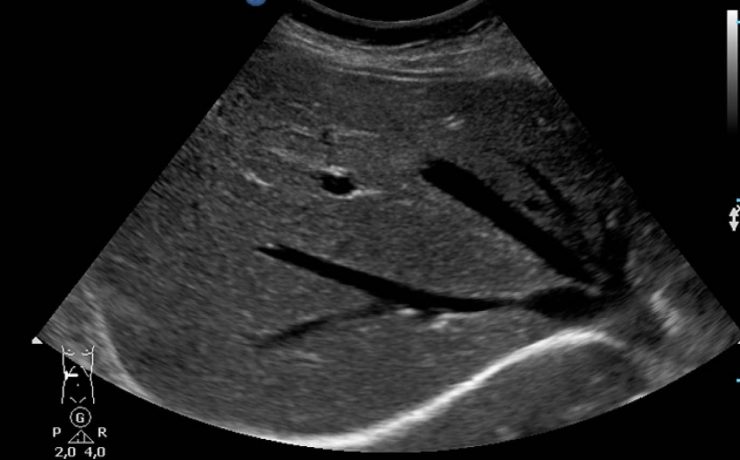

Carcinoma de vías biliares. Tumor de klatskin

Las estenosis malignas que involucran los conductos biliares pueden ser: Primarias ó propias de los conductos y canalículos biliares. Secundarias o por extensión desde otros órganos como el hígado, la vesícula, el páncreas, el duodeno ó ganglios linfáticos adyacentes. Ubicación Tercio superior: desde la confluencia hasta el hepático común Tercio